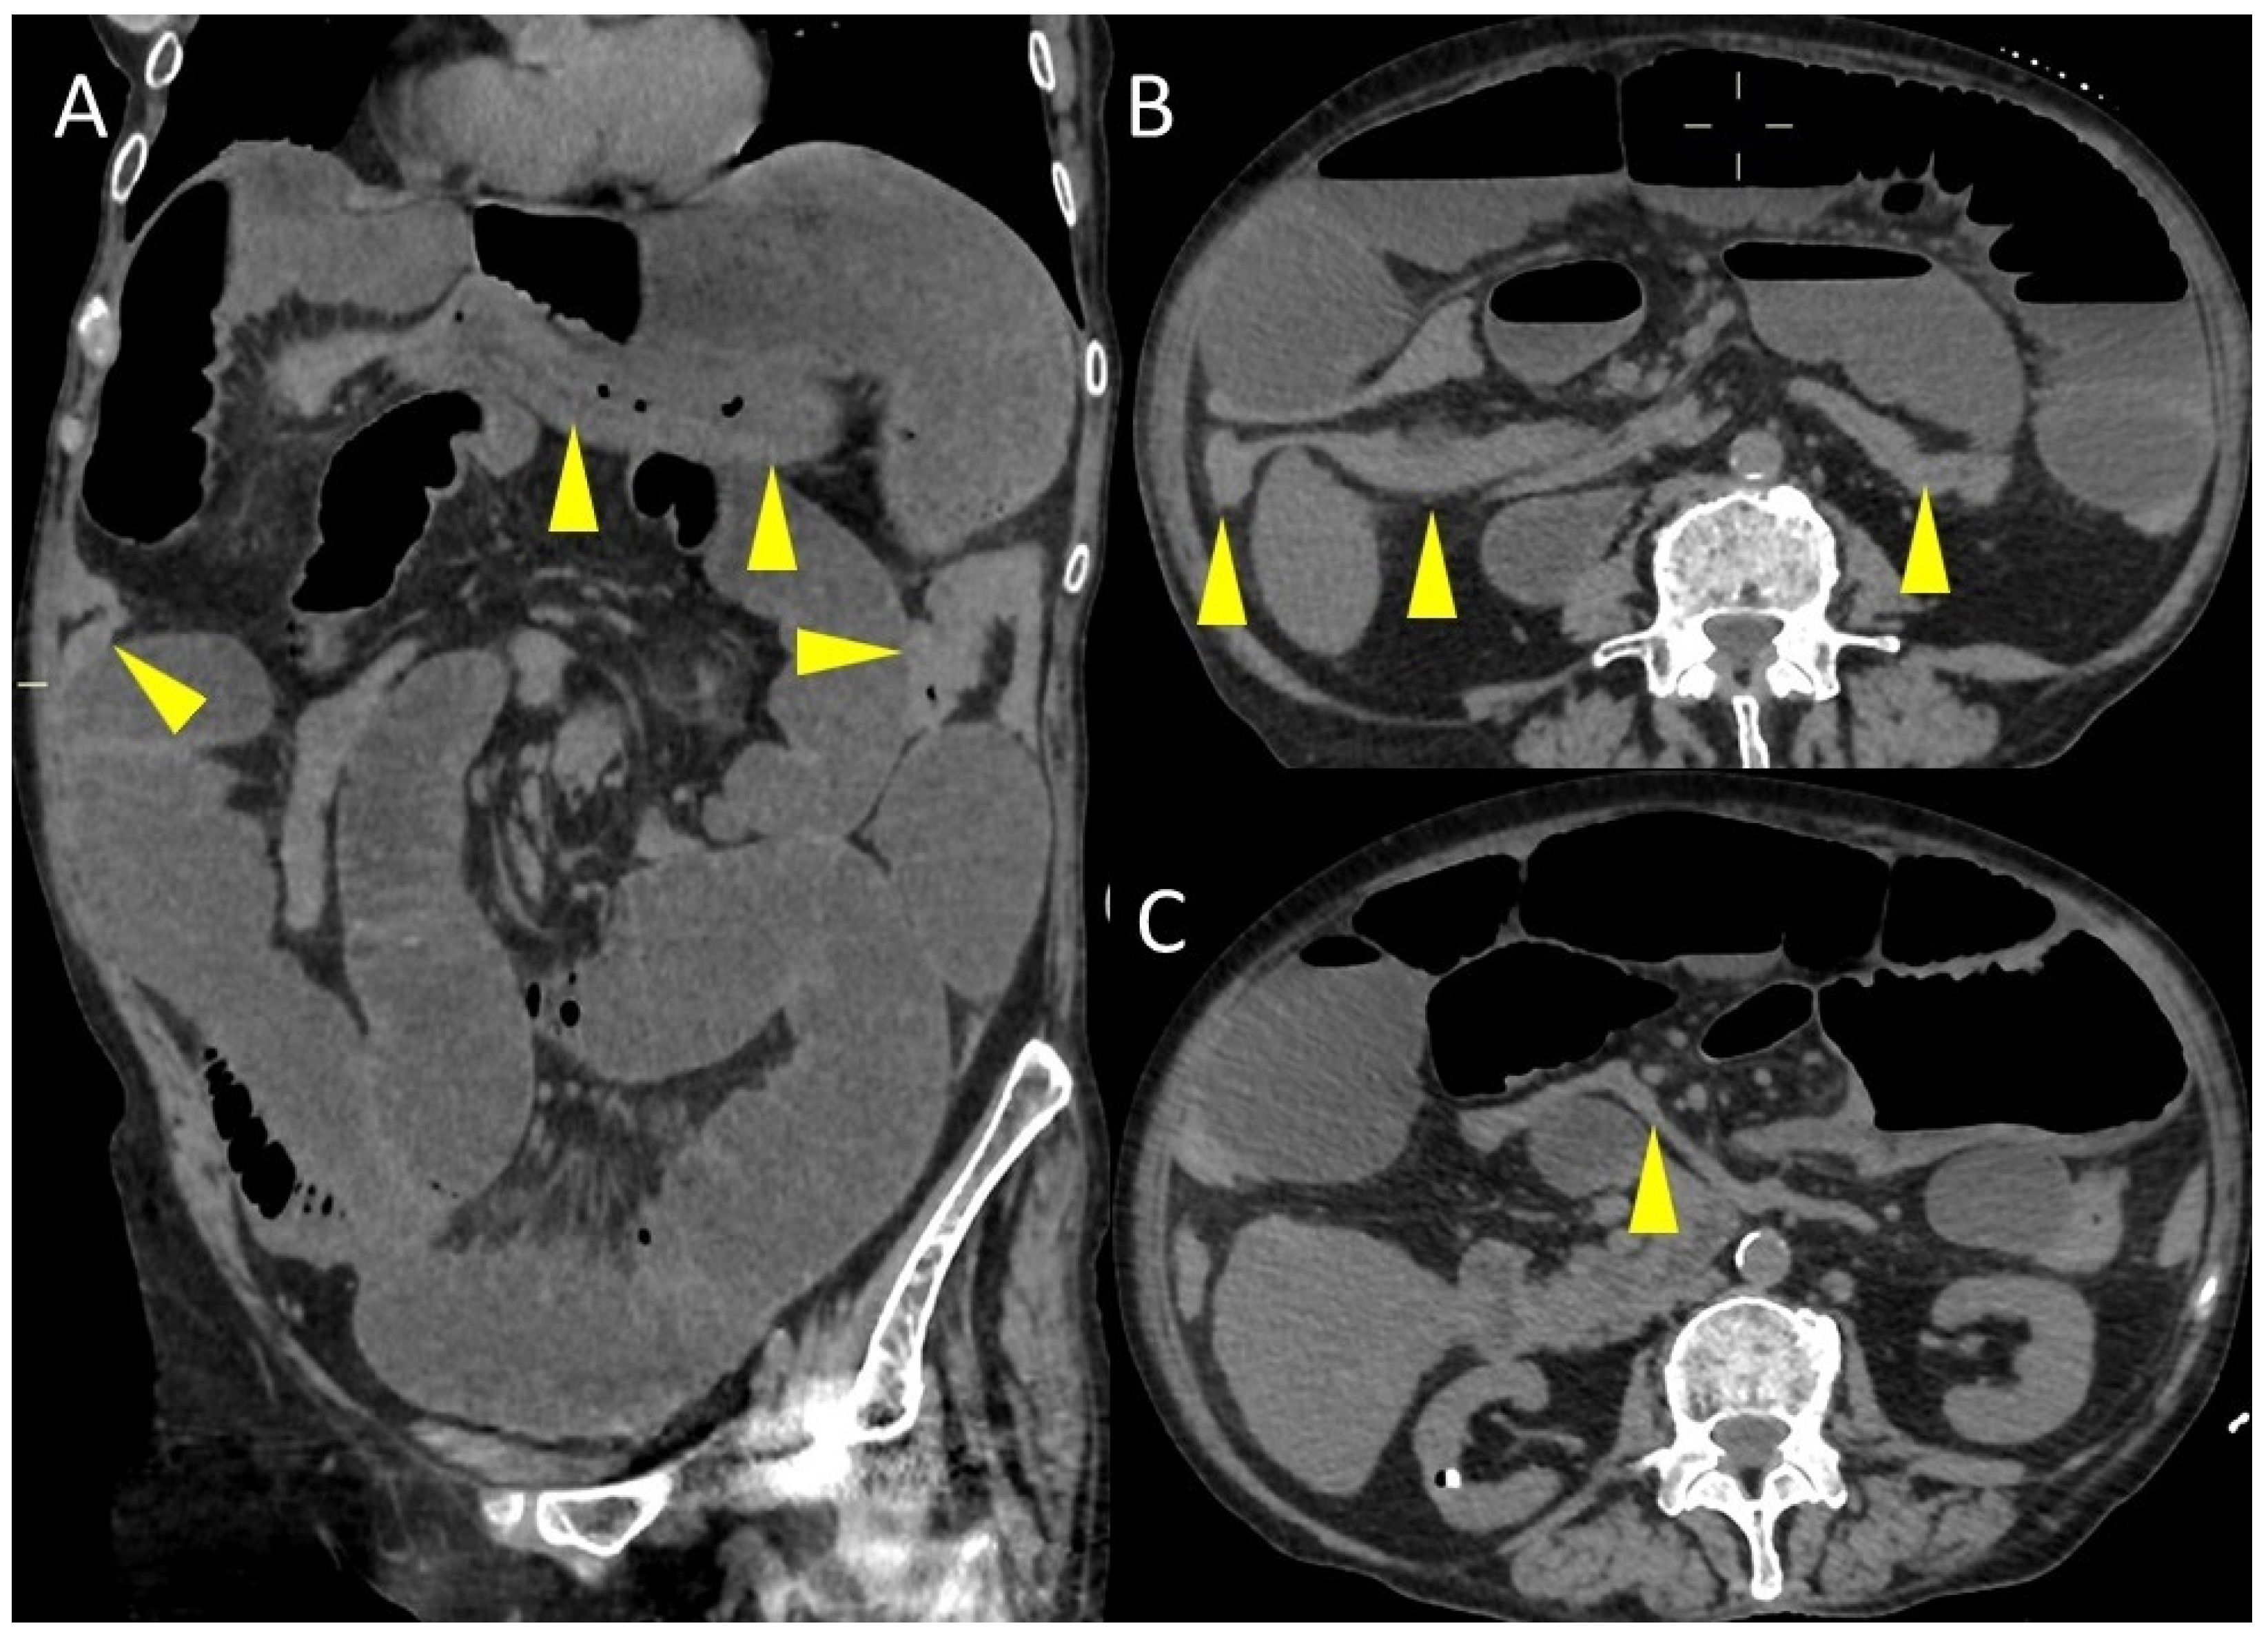

Embryo Sign on Abdominal CT as the Footprint of Cecal Volvulus: Improved Practice Through Lessons Learned from a Case Report

Pierro, A.; Posa, A.; Mirco, P.; Di Maio, D.; Vallo, A.; Lippi, M.; Cristino, R.; Barbieri, P.; Oriente, P.; Totaro, A.; et al. Embryo Sign on Abdominal CT as the Footprint of Cecal Volvulus: Improved Practice Through Lessons Learned from a Case Report. Life 2025, 15, 1873. https://doi.org/10.3390/life15121873